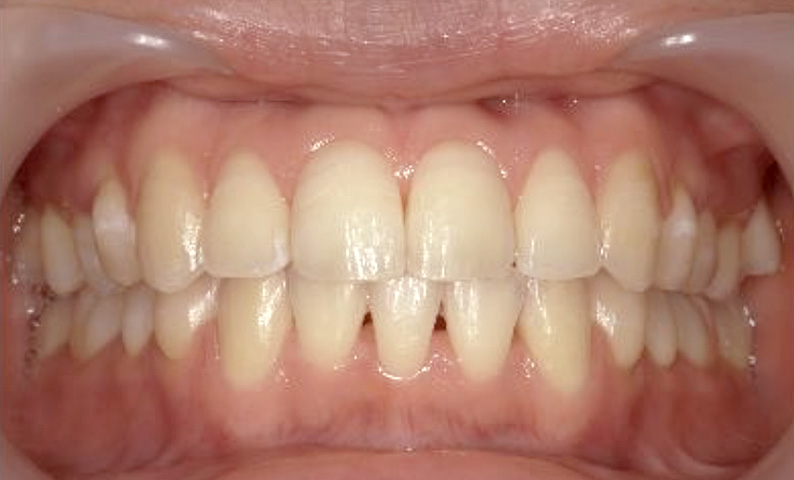

症例_020 上下顎の部分矯正

治療期間:6ヶ月金額:51万円+税女性前歯のガタガタ出っ歯

| Before | After |

|---|---|

|